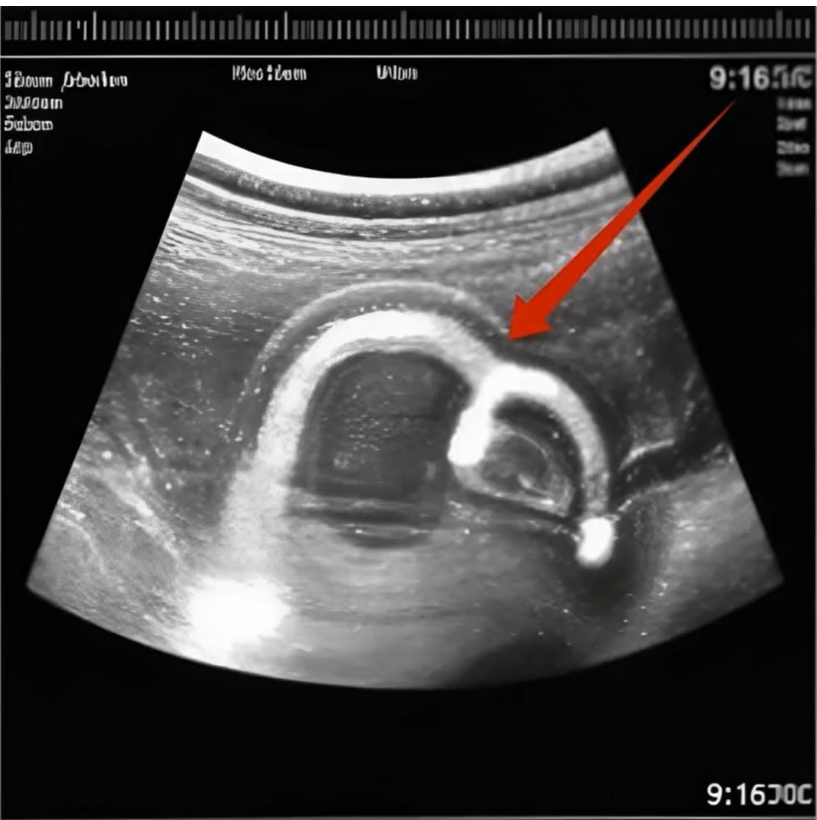

Nejdřív jsem si myslela, že se mýlím. Obraz byl nejasný, pohybující se. Ale pak to specialistka přiblížila.

Ruka.

Malá, jemná… ale jiná.

Měla víc prstů, než měla mít.

„Vaše dítě má vzácnou vývojovou odchylku,“ řekl klidně. „Nazývá se polydaktylie. Znamená to, že se vyvíjí více prstů, než je běžné.“